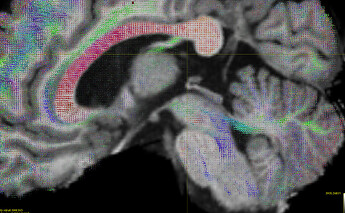

I am trying to perform probabilistic tractography on an in-house high-res (0.7 mm iso; b=1000 s/mm2; 60 directions plus 1 b0) dMRI dataset. I am using iFOD2 through a Singularity container built from the 3.0.8 Docker container.

I am interested in the cerebellar region, but am having trouble getting a result that satisfies me. My ODFs look OK, but when visualizing the tracking results, I get mostly broken streamlines, and my SCP and MCP look extremely poor. I am selecting 3.5 M streamlines in a bounding box that encloses my regions of interest.

FODs: